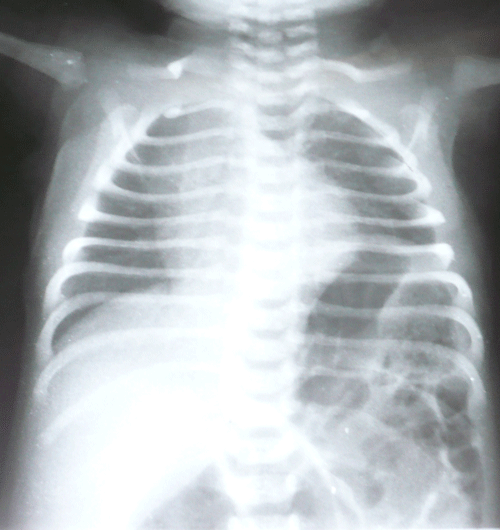

A 36-hour-old male neonate presented with imperforate anus and abdominal distension. There was no meconuria. Antenatal fetal anomaly scanning had not been done. Except for mild tachypnea (respiratory rate 60/min) physical examination of chest was nothing abnormal. Ultrasound of the abdomen did not reveal any anomaly. Invertogram (Fig. 1) showed a high variety imperforate anus. A sigmoid colostomy was performed. The colostomy started moving and patient was allowed orally the following day. The patient developed respiratory distress after starting feeds. A chest radiograph showed eventration of left hemidiaphragm (Fig. 2). A nasogastric tube inserted for gastric decompression alleviated the respiratory distress. The patient underwent plication of the diaphragm electively on 8th day of life. Postoperative recovery was uneventful. The patient is lost to follow-up.

Figure 1: High variety Imperforate anus. |